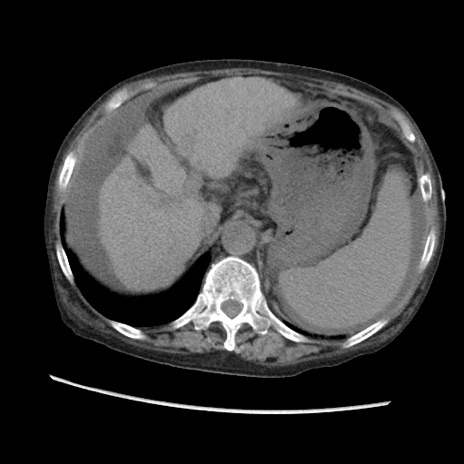

症例31(横断像)

【症例】80歳代 女性

【主訴】腹部膨満感

【現病歴】他院にて肝硬変にてフォロー中。1週間前から便秘、腹部膨満感、臍部腫瘤あり受診となる。

【既往歴】肝硬変

【身体所見】腹部膨隆あり、皮膚変化なし、疼痛なし。

【データ】WBC 4600、CRP 0.25